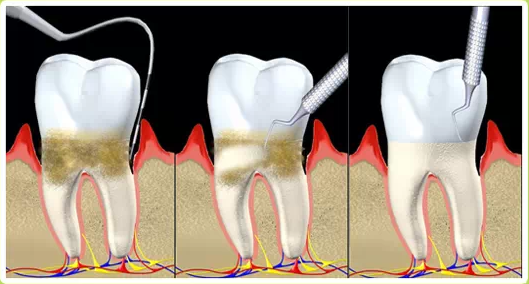

Toothbrushing is indeed the foundation of daily oral care, but its effectiveness is far from perfect . Even with diligent daily brushing, most people are unable to completely control the formation of dental plaque . Dental plaque is a biofilm composed of bacteria, food debris, and saliva that continuously reforms on the tooth surfaces . It particularly thrives in areas difficult to reach by toothbrushes, such as between the teeth (interproximal areas) and within the gingival sulcus .

Professional teeth cleaning, medically referred to as "supragingival scaling" , is the process of using specialized instruments to remove supragingival calculus (tartar), plaque, and stains from the teeth . Unlike daily brushing, professional cleaning can access and thoroughly clean areas that toothbrushes cannot effectively reach, such as the gumline and deep between the teeth, effectively removing established calculus and tenacious plaque deposits .